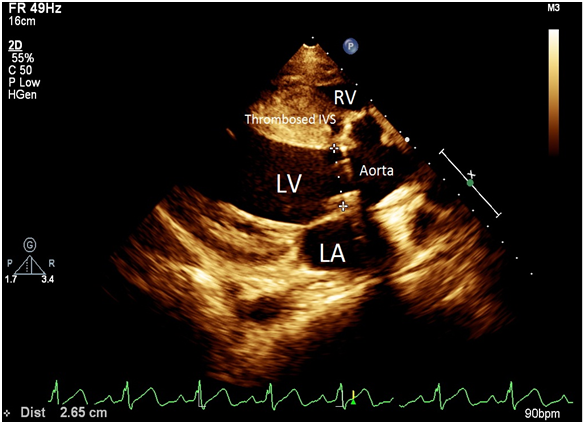

A 24 yrs old pleasant gentleman presented with history of gradually progressive shortness of breath and palpitation on exertion of 5 months duration. He also had history of 2 syncope 6 months prior. On examination he had wide pulse pressure with presence of peripheral aortic run off. Cardiac examination revealed displaced cardiac apex laterally with hyperdynamic apex beat, grade III early diastolic murmur over the aortic area. Rest of the examination was normal. Electrocardiogram revealed LBBB with first degree Atrio-Ventricular block with occasional ventricular premature beats. Chest X-Ray showed prominent bronchovascular markings. 2D echocardiogram revealed aneurysmal dilatation of right sinus of valsalva (SOV) which was burrowing and dissecting into interventricular septum (IVS) – echo free space as shown in Figure 1. LV was dilated with LVEDD of 5.4 cm and LVESD of 4.0 cm and reduced LV function (LVEF 40%). Aortic annulus was dilated (3 cm) and ascending aorta was of normal size. Aortic valve was tricuspid but deformed and calcified with evidence of severe aortic regurgitation. There was no communication of right sinus of Valsalva with any of the chambers. RA and RV were of normal size. TEE revealed same findings as in 2D echo, but both the right and left sinus of valsalva were seen dilated with the right coronary cusp (RCC) seen dissecting into the IVS with a nodular calcification in the vicinity of AoV as shown in Figure 2. Aortogram findings were also compatible with the 2D echo and TEE findings, which showed dilated right SOV without any evidence of leak into any of the chambers. Thereafter patient was taken up for aortic valve replacement along with repair and closure of the right sinus of valsalva aneurysm with Dacron patch. Intraoperatively there was a dilated right SOV with a cavity which led to the dissected IVS. The cavity was filled with calcium deposits and mural clots. The aortic side of the aneurysm was closed with Dacron patch, preserving the conduction system and avoiding the right coronary ostium. Post operative echo after 3 months showed completely healed and thrombosed aneurysmal sac of right SOV within the IVS as shown in Figure 3. There was no LV dilation (5 cms) with normal LV functions with normal functioning of the aortic prosthesis.

Figure 3: Healed and thrombosed aneurysmal sac of right SOV within the IVS.